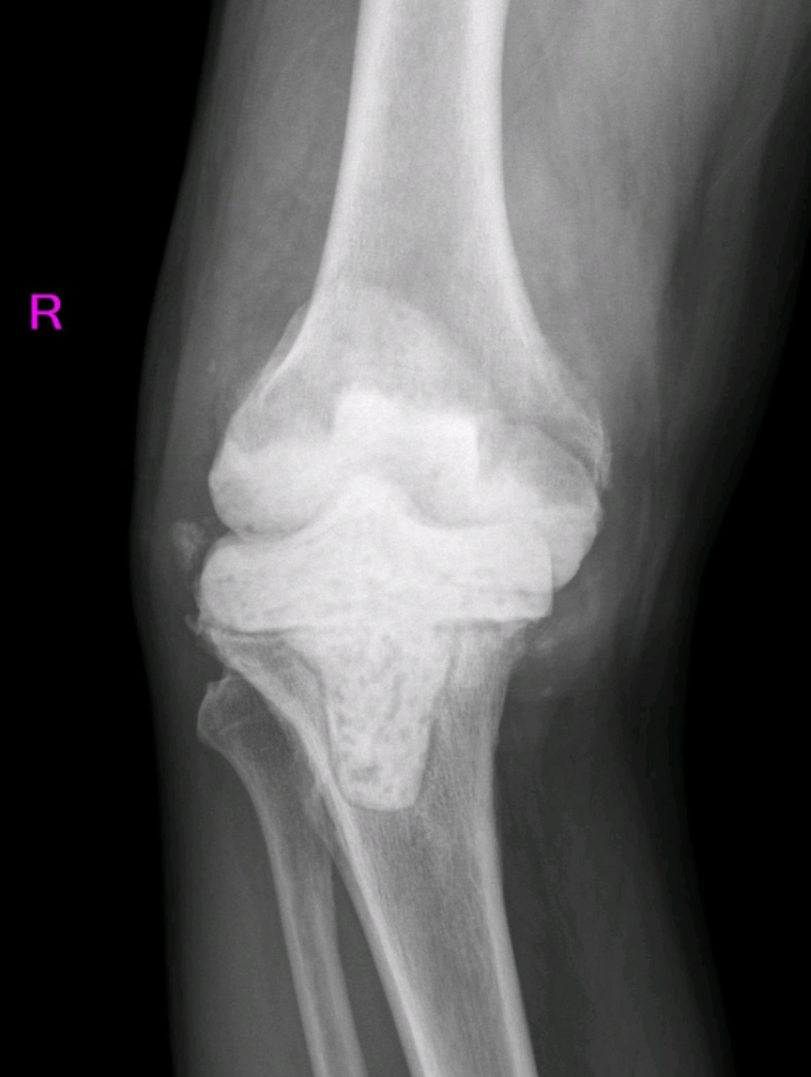

陈大叔两年前进行了全膝关节置换术,术后一年多出现了疼痛、体温高等症状,来院检查后发现是关节置换后感染。关节外科给他做了膝关节旷置术,经过半年多的恢复,查体发现血沉、C反应蛋白等感染指标都已恢复正常。近日,关节外科为其行膝关节翻修手术。

全膝关节假体翻修术前